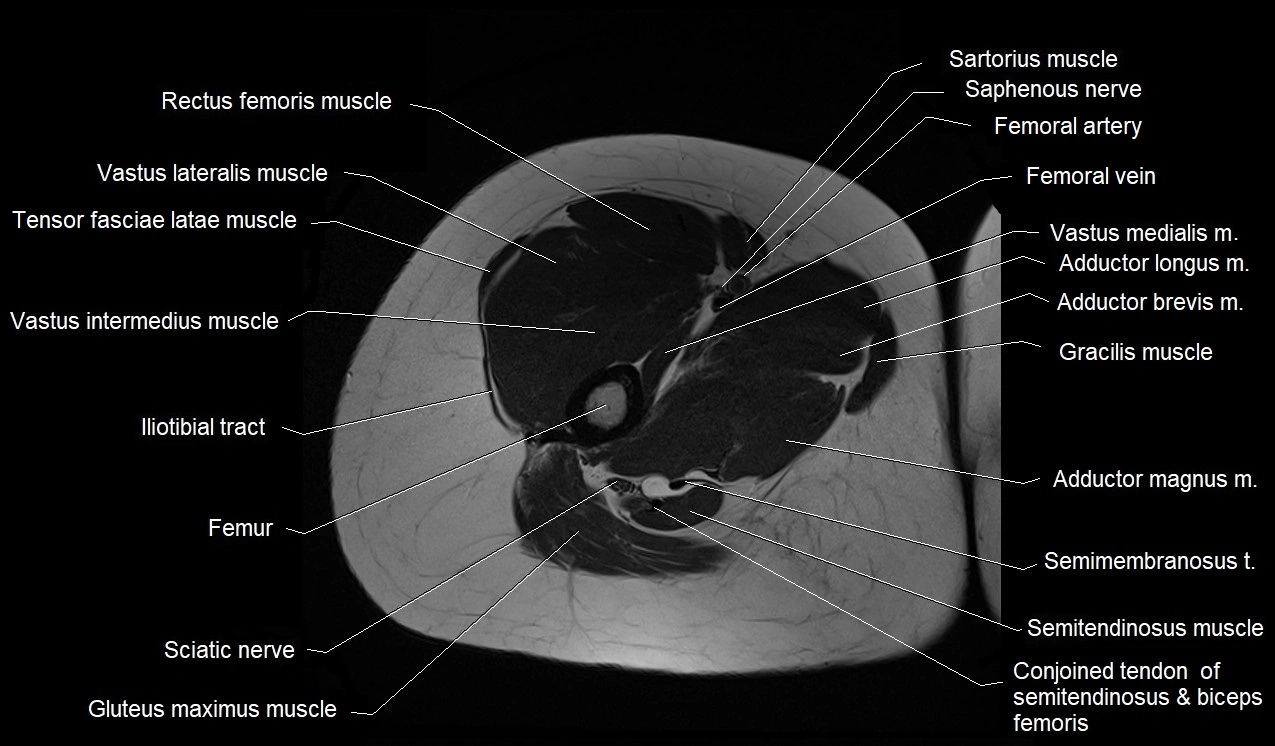

- Biceps femoris muscle (Long head)

- Conjoint tendon of biceps femoris & semitendinosus

- Femoral artery

- Femoral vein

- Gluteus maximus muscle

- Gracilis muscle

- Iliotibial tract

- Rectus femoris muscle

- Saphenous nerve

- Sartorius muscle

- Semimembranosus muscle

- Semitendinosus muscle

- Tensor fasciae latae muscle

- Vastus intermedius muscle

- Vastus lateralis muscle

- Vastus medialis muscle